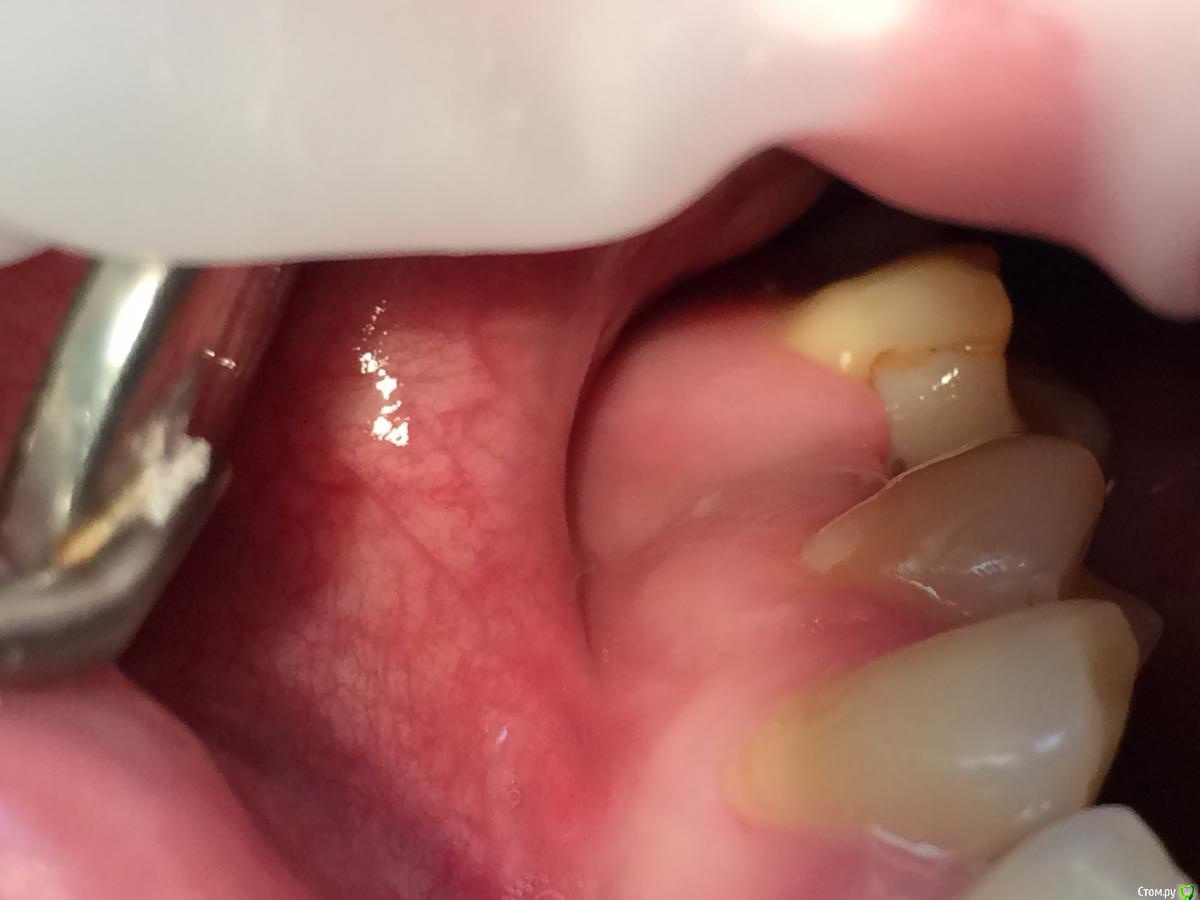

Graffwoman Опубликовано 25 февраля, 2018 Поделиться Опубликовано 25 февраля, 2018 Здравствуйте,уважаемые коллеги! Помогите кто-чем может)). Надо - очень срочно....(((8 дней назад установлен имплантат Osstem. Жалобы на сохраняющуюся одинаковую со дня вмешательства тупую,неприятную,ноющую боль в области проекции верхушки имплантата. Появляется примерно через 3 часа после пробуждения. Ротовые ванночки мирамистином и пьет нимесил 2 раза в сутки.Температура-36,4 *. Перед установкой хирург заметил небольшую полоску гноя из кармашка 26 (а,может,размягченые остатки пищи из под нависающего края пломбы 26,он был расположен под десной ,но похоже ,что гной). Операцию по установке откладывать не стали,пациент пополоскал рот и бетадином было обработано операционное поле.Четко понимаю,что отошли от протокола : не назначили антибиотикотерапию и осмотр на 3-й день произведен не был-так получилось..В анамнезе 3 года назад -двусторонний гайморит.Сейчас выделения из носа прозрачные только утром незначительное количество-то справа ,то слева. Когда появились не очень помнит,возможно до имплантации Антибиотики начал пить на 5- сутки после операции. При осмотре на 8-й день пальпация щеки и слизистой по своду переходной складки болезненна в одной точке чуть дистальнее проекции верхушки имплантата..Шов не состоятелен. В ране гнилостный запах .Обработали рану,хлоргексидином.На прицельном -пока спокойно.Это воспаление в мягких тканях без резорбции в периимплантной области ?Надо удалить имплантат , пока не поздно?Надежды никакой ? Посоветуйте,что делать,пожалуйста .С благодарностью надеюсь на ответ. Ссылка на комментарий

Graffwoman Опубликовано 25 февраля, 2018 Автор Поделиться Опубликовано 25 февраля, 2018 (изменено) внесу свою лепту Сосудосуживающий капли в нос на 10 дней - в каждый носовой ход Амоксиклав 1000 мг по 1 2 рд 5 дней либо супракс либо таваник - их легче принимать Бифиформ АциполНимесил 100 мг по 1 пакет 2 рд 7 дней Хлоргексидин или мирамистин - ротовые ванночки до 6 раз в день, потом сразу солкосерил дентальный наносить - он держится намного лучше других гелей и паст ,хватает трех раз в день Ну ,вообщем, это стандартный набор Из протокола хотел выяснить 1. чем сверлились ? был ли использован набор для закрытого синуса ?2. когда удаляли ( если это были Вы ) качественно ли был выполнен корежат?3.торк ?не вижу смысла трогать имплантат сейчас .Пусть заживает вторичным натяжением .Приживется - хорошо ,нет - переставите .Спасибо1.Стандартный набор Osstem2.Хороший вопрос.Прошло 1,5 года с момента удаления.Причину удаления сходу не вспомню ,но процесс был хроническим,без признаков воспаления.На верхушке корня после удаления была прикрепленная гранулема. .Кюретаж был ,как считали тогда- легкий (гранулема то вышла ),но качественный.Проба на соустье после удаления отрицательная.Сгусток формировался слабо,в лунку рыхло положила губку с йодоформом. Неожиданно лунка заживала плохо,вялотекущий альвеолит. Дополнительный неагрессивный кюретаж и промывание ХГ. .Но.... Через год- КТ и поняли,что кость не полноценная. На слизистой десны вроде легкое углубление-точка. Не придали значения,может,ревизию надо было сделать??? .Больше насторожил обьем слизистой в пазухе-до 25 мм,на сегодня -до 10). Долго ходил по ЛОРам -толку никакого. Решили оставить в надежде,может кость сформируется.,теперь снова вернулись.Всю остальную историю уже знаете. Прилагаю снимок первого КТ, по поводу размытой границы гайморовой -ничего пока не могу сказать,кажется,это просто такой ракурс. .3.Торк 45Сейчас принимает ципрофлоксацин третьи сутки по 500 мг 2р/д,антигистаминные, нимесил получается 2р/д,(тк к вечеру стал ныть снова),противогрибковые и для флоры кишечника. Как думаете ,а боль в проекции верхушки имлантата -откуда ? Изменено 25 февраля, 2018 пользователем Graffwoman Ссылка на комментарий